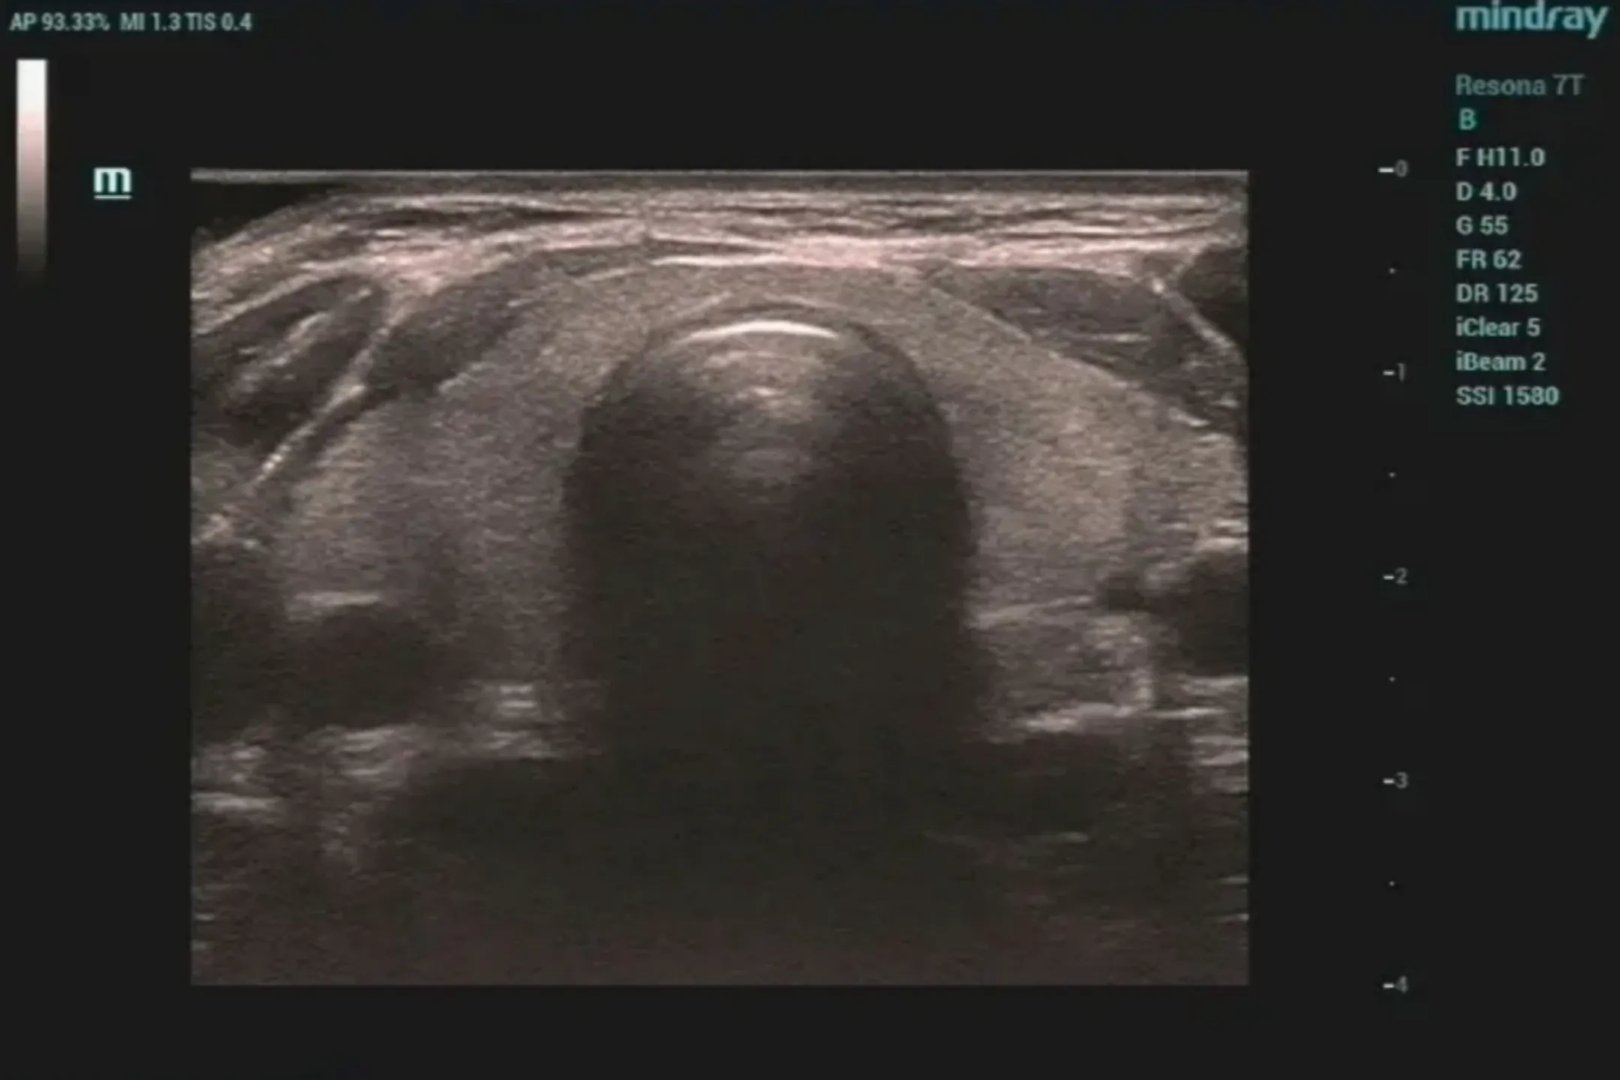

的有关信息介绍如下:彩超是彩色多普勒超声的简称,可对血管、腹腔脏器、心脏、子宫及附件、小器官、前列腺及精囊等全身性脏器进行检查。